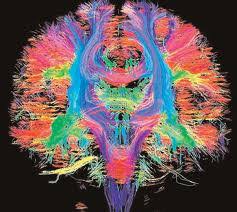

Chụp cộng hưởng từ khuếch tán sức căng ( Difusion tensor imaging: DTI ) hay chụp cộng hưởng từ các bó sợi Thần kinh (Tractography) là một kỹ thuật Chẩn đoán hình ảnh hiện đại trong tạo ảnh cộng hưởng từ để đánh giá bệnh lý thần kinh. DTI là một kỹ thuật MRI sử dụng khuếch tán dị hướng để ước tính tổ chức sợi trục chất trắng của não. Chụp cộng hưởng từ bó sợi là một kỹ thuật tái tạo 3D để đánh giá các dây thần kinh sử dụng dữ liệu được thu thập bằng hình ảnh sức căng.

Mục đích của chụp chuỗi xung này là đánh giá các tổn thương sợi trục của não, tủy sống hoặc tìm liên quan giữa tổn thương và các bó sợi thần kinh để tránh làm tổn thương các bó sợi thần kinh khi điều trị các tổn thương.

Các ứng dụng của chụp bó sợi thần kinh đang phát triển mạnh vì kỹ thuật này rất nhạy với những thay đổi ở cấp độ tế bào và vi cấu trúc.